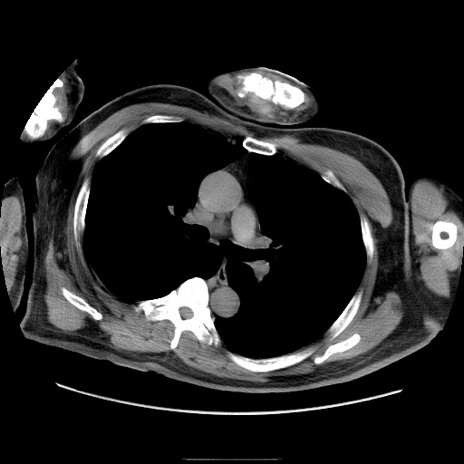

症例22(横断像)

【症例】50歳代男性

【主訴】腹痛

【現病歴】AVMからの被殻出血のため回復期リハ病棟入院中。 本日午後3時頃急に下腹部痛が出現した。

【既往歴】AVM、被殻出血、虫垂炎、高血圧

【身体所見】意識晴明、左半身不全麻痺、会話の理解は良好、36.5°C、腹部:膨隆、全体に板状硬、下腹部正中に圧痛点あり、反跳痛-、筋性防御不明、右下腹部にope scar

【データ】WBC 9400、CRP 0.06